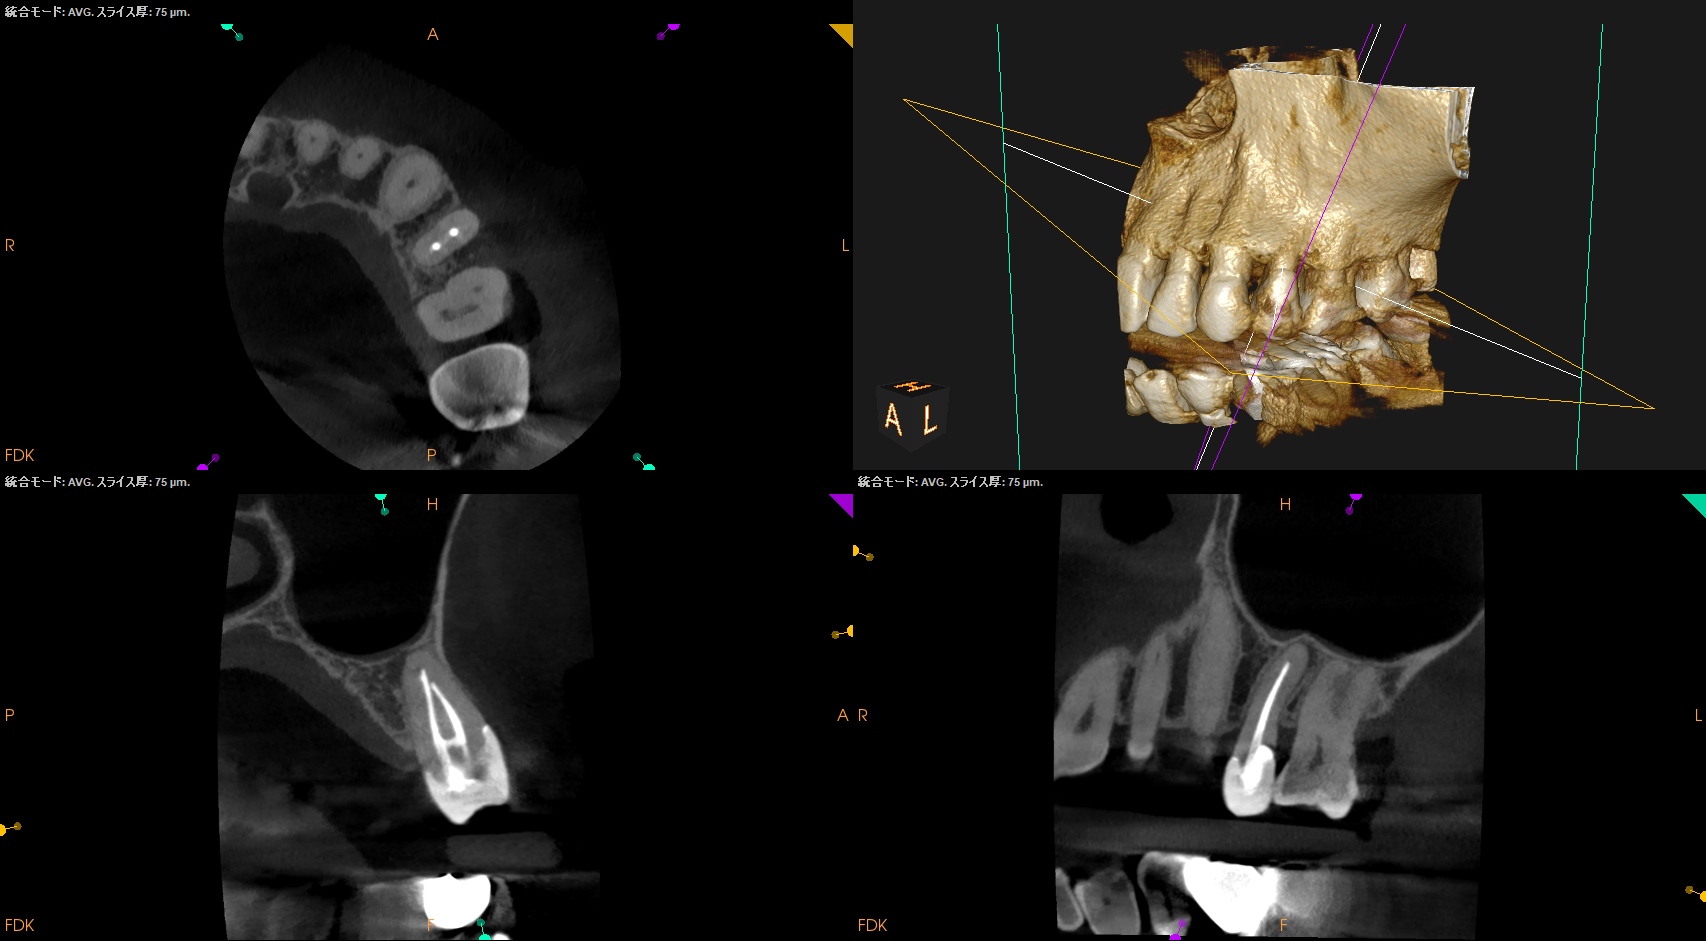

#13 Apicoectomy(2025.10.7)

私には歯根が透けて見えるが、皆さんはどうだろうか?

思しき部位をOsteotomyした。

すると、Apexが顔を出したので3mm Root resectionした。

メチレンブルーで染色後にRetroprep, Retrofillした。

術後にPA, CBCTを撮影した。

問題はないだろう。